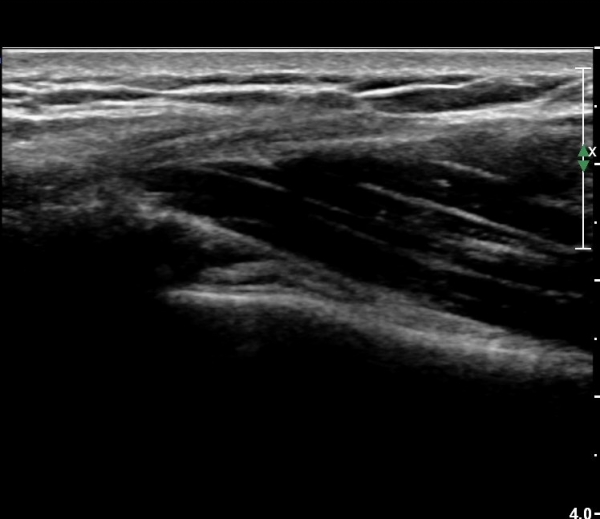

ȸÀü±Ù°³°£°Ý(rotator cuff interval) Ⱦ´Ü¸é°Ë»ç¿¡¼­ °ß°©ÇϱٰǻóºÎ¿Í ±Ø»ó°Ç ³»ÃøºÎ¿¡

ƯÀÌ ¼Ò°ßÀ» º¸ÀÌÁö ¾Ê´Â´Ù(»çÁø 1, 2).